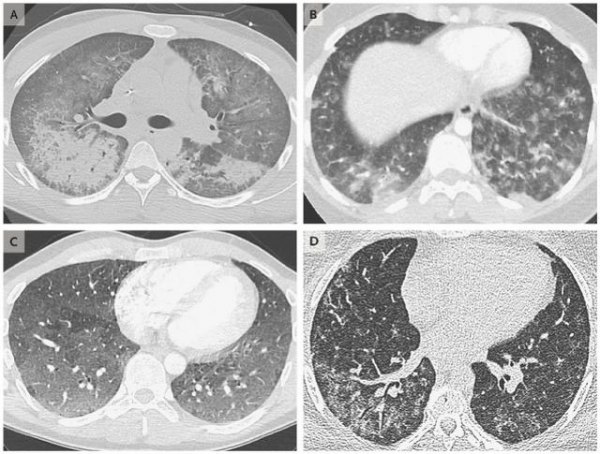

2019年7月,美國威斯康星州大規模暴發“電子煙疾病”,患者的肺部CT部分區域呈現團狀模糊的白色,三分之二的患者在18歲到24歲之間,已有超2000起肺損傷病例和59例死亡病例被歸類為與電子煙相關。然而,相關確切病因等信息仍不明晰。

通常,病例在經歷幾天類似流感或肺炎的癥狀之后來到急診室,患者的肺部CT部分區域呈現團狀模糊的白色。七成病例是男性,三分之二的患者在18歲到24歲之間。